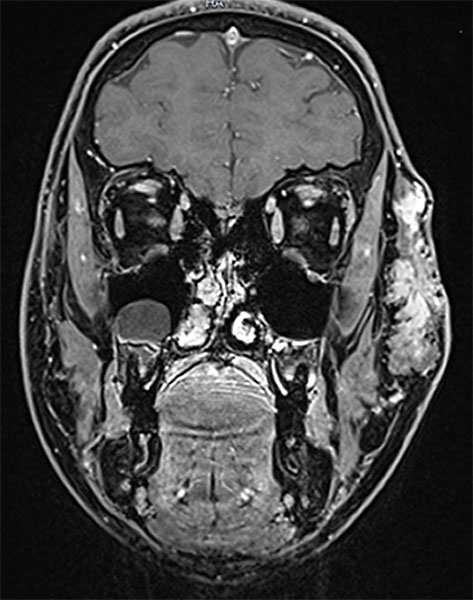

Coronal, T2-weighted fat-suppressed MRI of the face. The venous malformation typically appears very hyperintense (white).

Axial, T2-weighted fat-suppressed MRI of the face. The venous malformation appears typically very hyperintense here too. No expansion into the depth.

Coronal, T1-weighted MRI of the face. The venous malformation appears isointense to the musculature and is embedded in the surrounding fatty tissue.

Coronal, contrast-enhanced, dynamic MR angiography, MIP imaging 33 s after injection of the contrast medium. The contrast dynamic is in the venous phase, the venous blood vessels are fully contrasted. The venous malformation itself does not accumulate any contrast medium at this time.

Coronal, contrast-enhanced, dynamic MR angiography, MIP displayed 124 s after injection of the contrast agent, thus a late venous phase. Only now does the venous malformation slowly accumulate some of the contrast medium (“pooling”).

Coronal, T1-weighted fat-suppressed MRI of the face after administration of contrast medium. The venous malformation enriches the contrast medium more clearly after 4 minutes, but relatively slowly and not yet completely at the time of imaging.

Axial, T2-weighted MRI of the face (without fat suppression). The venous malformation is highly hyperintense and shows fluid-fluid levels.